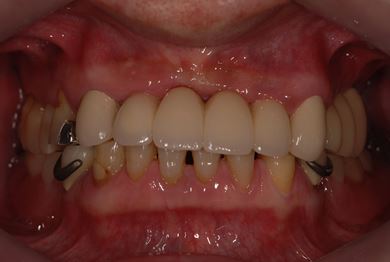

インプラントの症例写真 IMPLANT

骨再生スピードインプラント治療+セラミック治療

| 治療方針 | 上前歯部は、抜歯と同時にインプラントを埋入し、治療期間を短縮する。左上奥は、ソケットリフトにて上顎洞を拳上し、インプラント治療を可能にする。 | ||||||||||||||||||||||||||||||||

| 治療内容 | インプラント4本(ソケットリフト・抜歯即日)、テンポラリーインプラント2本、メタルボンドクラウン9本 | ||||||||||||||||||||||||||||||||